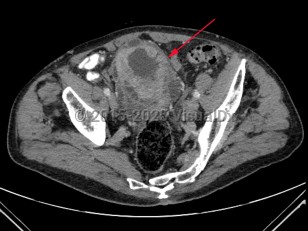

Rectal carcinomaRectal carcinoma

Metastatic pancreatic carcinomaMetastatic pancreatic carcinoma